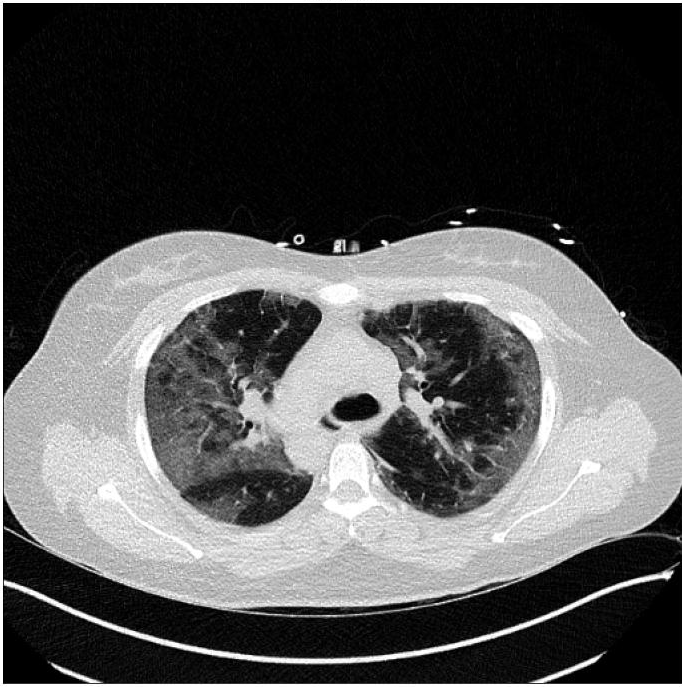

(a) Lung CT scan

The resultant segmentation map of FuDSA-Net is observed to be relatively more accurate and closer to the corresponding ground truth, as illustrated in Fig. 3.